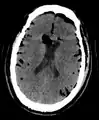

CT scans of patients with a tension pneumocephalus typically show air that compresses the frontal lobes of the brain, which results in a tented appearance of the brain in the skull known as the Mount Fuji sign.[1][2][3] The name is derived from the resemblance of the brain to Mount Fuji in Japan, a volcano known for its symmetrical cone. In typical cases, there is a symmetrical depression near the midline (such as the crater of a volcano), due to intact bridging veins.[3] Its occurrence seems to be limited to tension pneumocephalus (not occurring in pneumocephalus without tension).[4] The sign was first described by a team of Japanese neurosurgeons.[5]

Large pneumocephaly secondary to surgical wound

Pneumocephaly